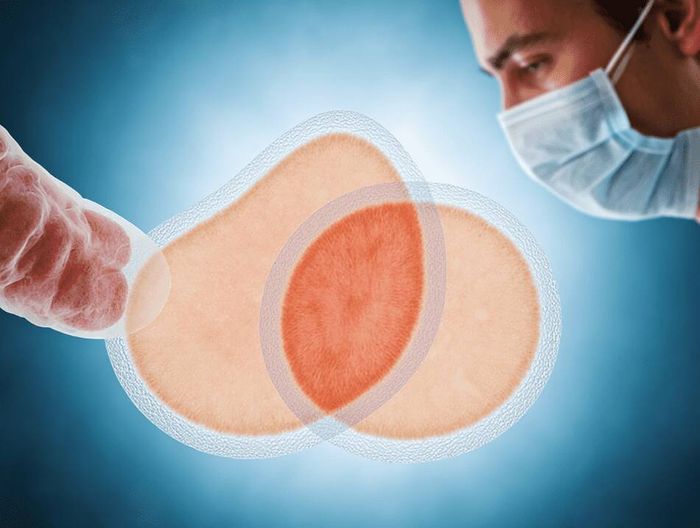

在医疗器械检测领域,生物相容性检测指通过细胞毒性、致敏、刺激等试验,评估材料与人体接触时的安全性,考察是否引发炎症、过敏等反应,是确保器械临床使用安全的关键检测。

其核心是依据相关标准,验证材料与人体组织的相容性,降低不良反应风险,为医疗器械的生物安全性评价提供科学依据。